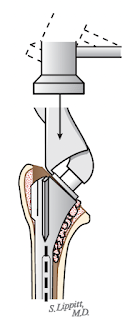

Stress shielding can be a problem when an implant is fit tightly against the distal cortical bone.

The use of a thin stem enables proper seating of the component

.

avoiding the issue of incomplete seating that can be seen with a large stem

Because the shaft is not weakened, the thin stem with impaction grafting technique minimizes the risk of intraoperative and postoperative fractures.